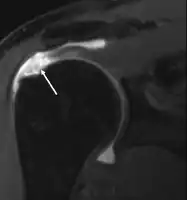

МРТ

Магнитно-резонансная томография (МРТ) и ультразвук[39] сравнимы по эффективности и полезны в диагностике, хотя оба имеют ложноположительный уровень 15-20 %.[40] МРТ может надёжно обнаружить большинство разрывов на всю толщину, хотя очень маленькие точечные разрывы можно не заметить. В таких ситуациях МРТ в сочетании с инъекцией контрастного вещества, МР-артрограмма может помочь подтвердить диагноз. Следует понимать, что обычная МРТ не может полностью исключить небольшой разрыв (ложноотрицательный результат), в то время как разрывы частичной толщины не могут быть обнаружены с такой надежностью.[41] Хотя МРТ чувствительна к выявлению дегенерации сухожилия (тендинопатии), она не может надежно отличить дегенеративное сухожилие от частично разорванного сухожилия. Опять же, магнитно-резонансная артрография может улучшить дифференциацию.[41] Её общая чувствительность — 91 % (то есть 9 % ложноотрицательных результатов), таким образом магнитно-резонансная артрография является надёжной при обнаружении разрывов частичной толщины вращающей манжеты манжеты.[41] Однако его обычное использование не рекомендуется, поскольку оно связано с введением в сустав иглы с потенциальным риском заражения. Следовательно, тест предназначен для случаев, когда диагноз остается неясным.